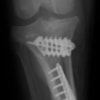

術後左後肢側面像

術後左後肢正面像

術前のTPAは左後肢33.1°右後肢26.8°でしたがTPLO実施により左後肢5.5°右後肢12°に矯正されました。

手術前後のTPA(脛骨高平部の角度)を測定しています。

約29°から約10°へ矯正されています。